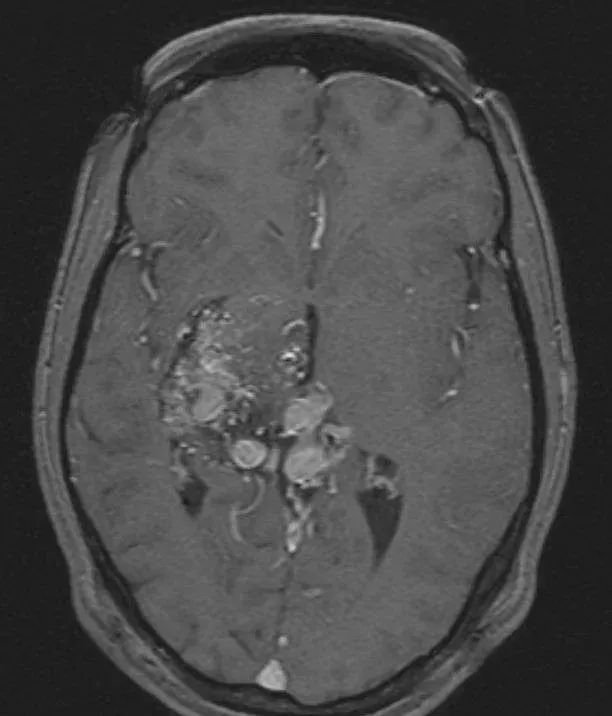

轴位T1加权像,既往行γ刀治疗

直到在她36岁这一年,她和小女儿玩闹时候突发头痛,送医检查后发现丘脑/基底节AVM出血,Spetzler-Martin分级为 6 级,这意味着她的病情手术难度非常大,预后也会很差。